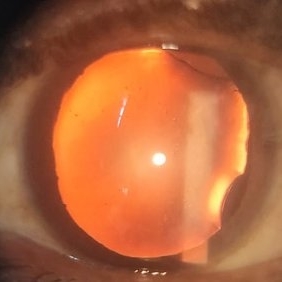

Traumatic Subluxation of lens

Apr 24 2015 by Mehul A Shah

23-year-old male presented with history of blunt trauma and diminished vision.

Photographer: Mehul Shah, Drashti Netralaya

Imaging device: FORUS

Condition/keywords: blunt trauma, globe perforation, subluxation of lens